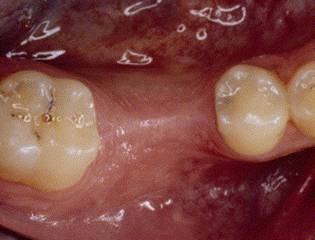

1 ST PREMOLAR EXTRACTION

4 MONTH HEALING